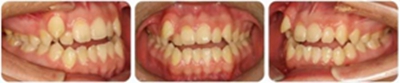

張某,男性,13歲,主訴前牙反頜伴開頜,要求矯治。

正面觀雙側(cè)基本對(duì)稱,垂直向基本協(xié)調(diào);側(cè)面觀直面型,下頜平面角較陡。顳下頜關(guān)節(jié)未見異常。

恒牙列,上中線右偏2mm,下中線左偏3mm,左側(cè)尖磨牙Ⅰ類 ,右側(cè)尖磨牙Ⅲ類。前牙反頜,13唇側(cè)低位萌出。上牙列擁擠度10mm,下牙列擁擠4mm。

(1)安氏Ⅲ類亞類錯(cuò)合;

(2)前牙開頜、反頜;

(3)13唇側(cè)低位萌出。